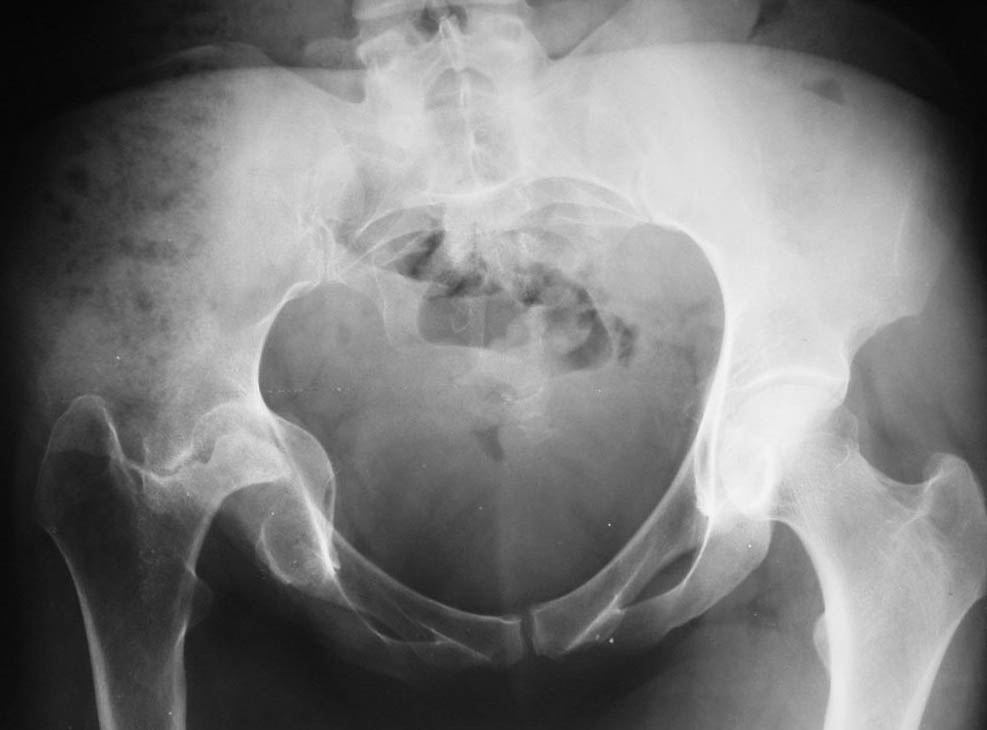

Уважаемые коллеги! Окажите, пожалуйста, консультативную помощь! Женщина 32 лет. Последствия перенесенного правостороннего гнойного коксита. Коксит явился следствием абсцесса правой паховой области развившегося после введения наркотиков в паховые сосуды. Наркотики не употребляет с 2000 года. Свищ закрылся год назад. В настоящее время в правой паховой области имеется рубец, спаянный с горизонтальной ветвью лобковой кости. Признаков воспаления нет. Нога не опорна из-за порочной установки. Вопрос: тотальное эндопротезирование или корригирующая остеотомия бедренной кости ? Заранее благодарю! С уважением,А.В.ВладзимирскийДонецкий НИИ травматологии и ортопедииДонецк, Украина